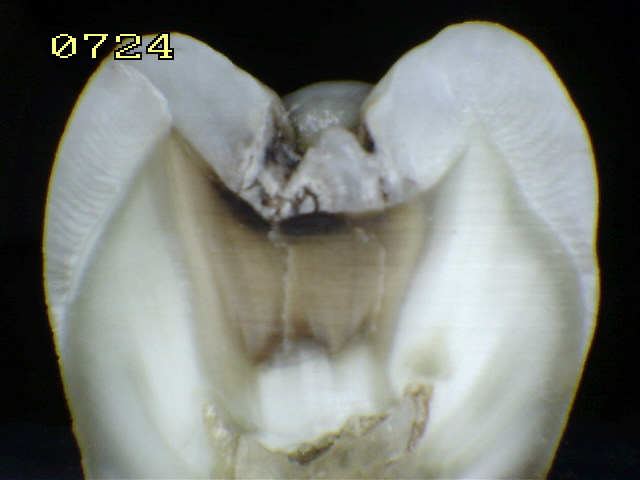

Espécimen Nº 12 |

|

Lesión característica de un código 4 |

Esquema del corte sagital |

Se

verifica un código 3

histológico

Observe en el corte sagital

la vitalidad pulpar, debido a que las fotografías y el corte

se hicieron a unas pocas horas de la

exodoncia, conservando así la humedad natural del diente. |